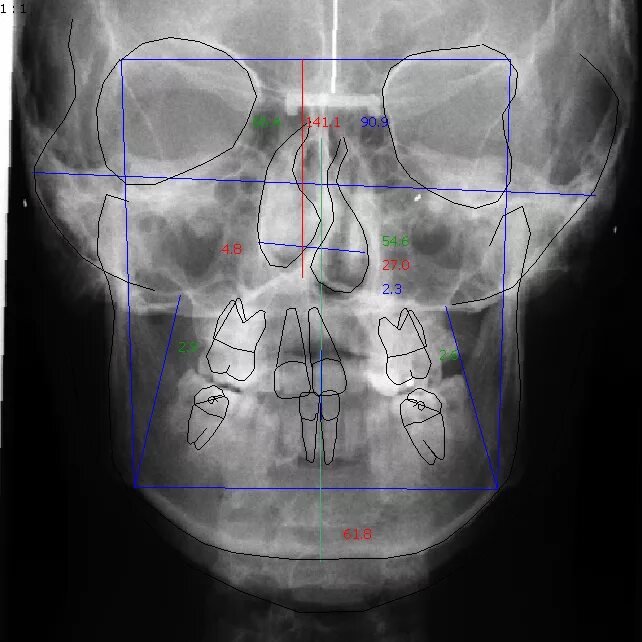

Снимок в прямой проекции